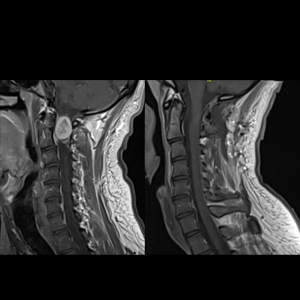

Spinal stenosis (Lumbar) Spinal stenosis (Cervical) Spinal stenosis (Thoracic) Lumbar Disc Herniation Spondylolisthesis Cervical Foraminal Stenosis Vertebroplasty Lumbar Fusion Anterior Cervical Fusion (ACDF) Posterior Cervical Fusion Thoracic Fusion Revision Lumbar Fusion Surgery Facet Joint Cyst Spinal Tumour Minimally Invasive Lumbar Fusion (XLIF) Minimally Invasive Lumbar Fusion (ALIF) Lumbar Fusion (TLIF) Thoraco-lumbar Fusion Lumbar Corpectomy Complex Lumbar Spine Surgery (Spino-pelvic fixation) Complex Cervical Spine Surgery Complex Thoracic Spine Surgery Occipito-cervical Fusion Minimally invasive surgery for thoracic disc herniation Other Related Topics